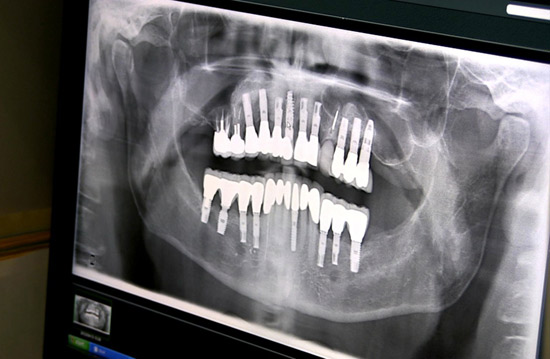

I was lucky – with much support - I commenced a complete dental reconstruction in 2005 - bone grafts, 17 implants and a strong set of gleaming new teeth.